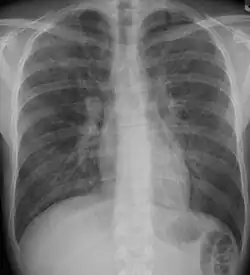

A chest x-ray is 63% sensitive and 93% specific for ILD.[10] With advances in computed tomography, CT scans of the chest have supplanted lung biopsy as the preferred diagnostic test for ILD. A thoracic CT scan is 91% sensitive and 71% specific for ILD.[10] In higher income countries, less than 10% of people with ILD undergo a lung biopsy as part of the diagnostic evaluation.[16]

Chest radiography is usually the first test to detect interstitial lung diseases, but the chest radiograph can be normal in up to 10% of patients, especially early in the disease process.[19][20]